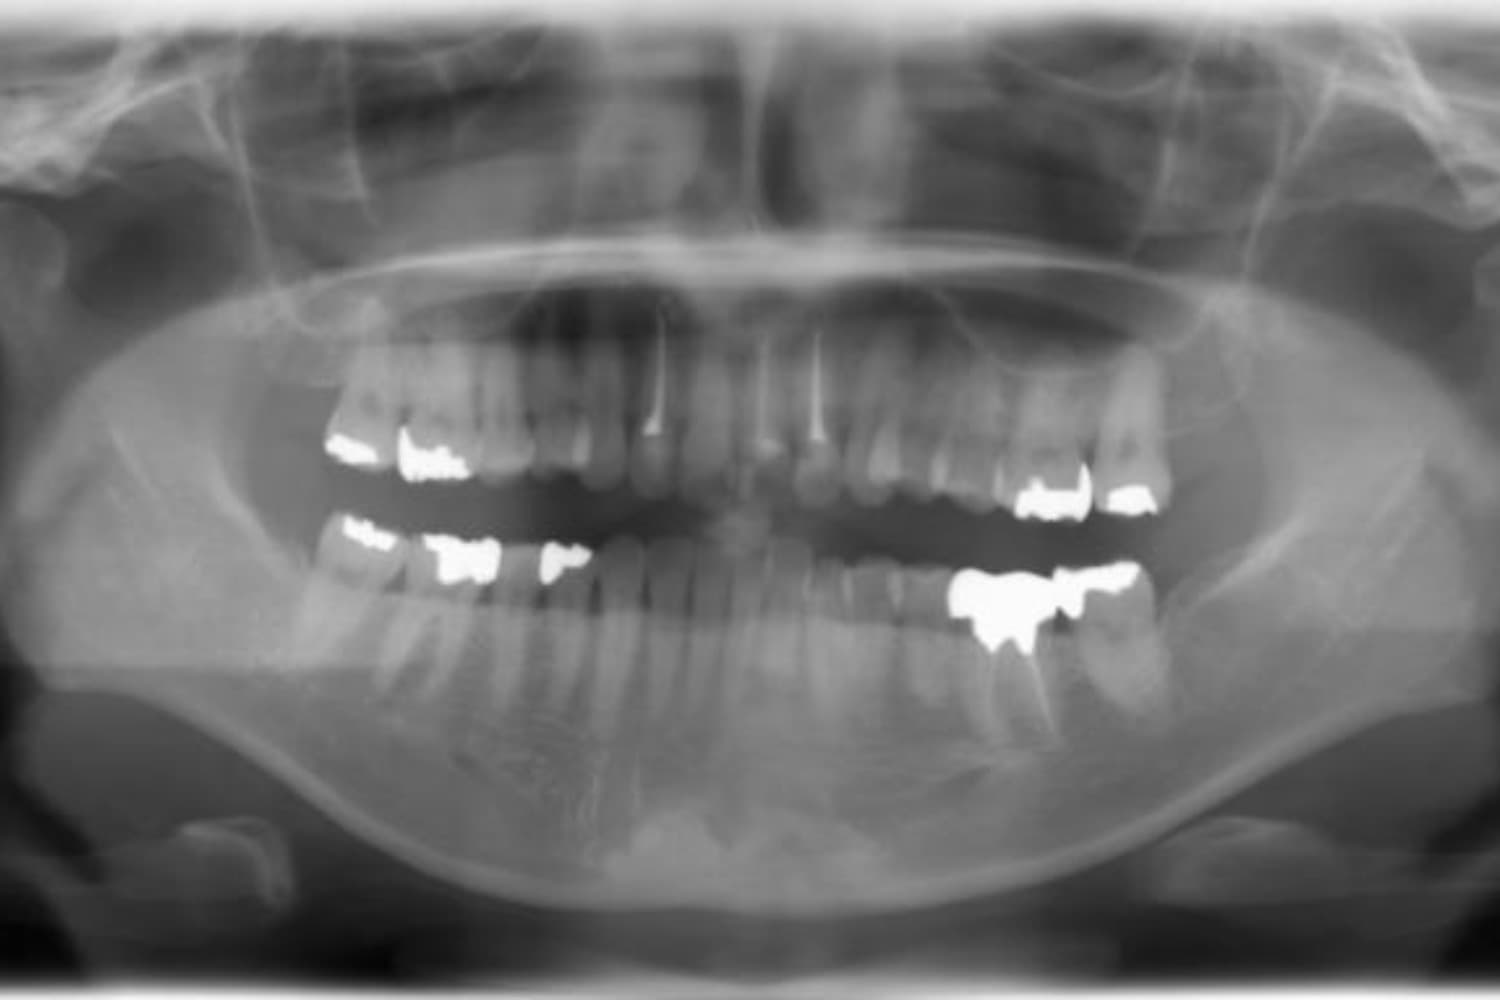

上顎前歯1本欠損症例(1)

Before

After

歯の根が割れていたため抜歯をおこないました。インプラント・ブリッジ・義歯それぞれのメリットやデメリットをお話させていただき、インプラントでの治療を選択されました。

年齢

46歳

性別

女性

主訴

前歯の色味が気になる

治療期間

11ヵ月

費用

60万円

副作用・リスク

インプラント治療は外科的な処置を伴い、多少の腫れや痛みが出ることがあります。 多くの場合は鎮痛薬で和らげることができます。

口腔内やその周辺の立体画像が得られるCT装置です。治療の精度を高めるために必須の装置です。